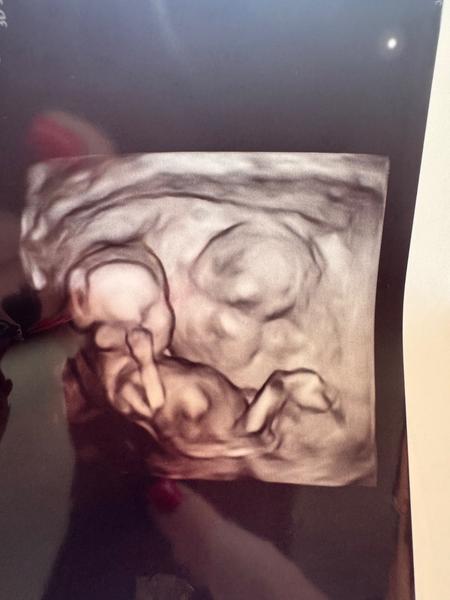

Může být ve čtrnáctém týdnu poznat pohlaví dítěte?

Ahojky,co myslíte může to být kluk nebo spíš holka?Nebo nejde to ještě poznat.Jsem 14 týdnů

Mi lékař na 90 % odhadl pohlaví už na prvním screeningu (a správně), takže věřím, že s dobrou technikou a zkušenostmi lékaře to poznat lze.

Nám u obou dětí řekl lékař odhad pohlaví již na tom prvním screeningu, vždy teda bylo řečeno, že to máme brát trochu s rezervou, ale v obou případech byla trefa a pohlaví se neměnilo. U toho druhého doktora, to je kapacita v oboru, se říkalo, že když si není jistý, tak to prostě neříká. Důležité je, jak je mimčo natočené, jak se ukazuje, je důležité vidět pohlavní hrbolek a jeho sklon (pokud "trčí" směrem nahoru = kluk, pokud je spíš rovnoběžně s páteří = holka)